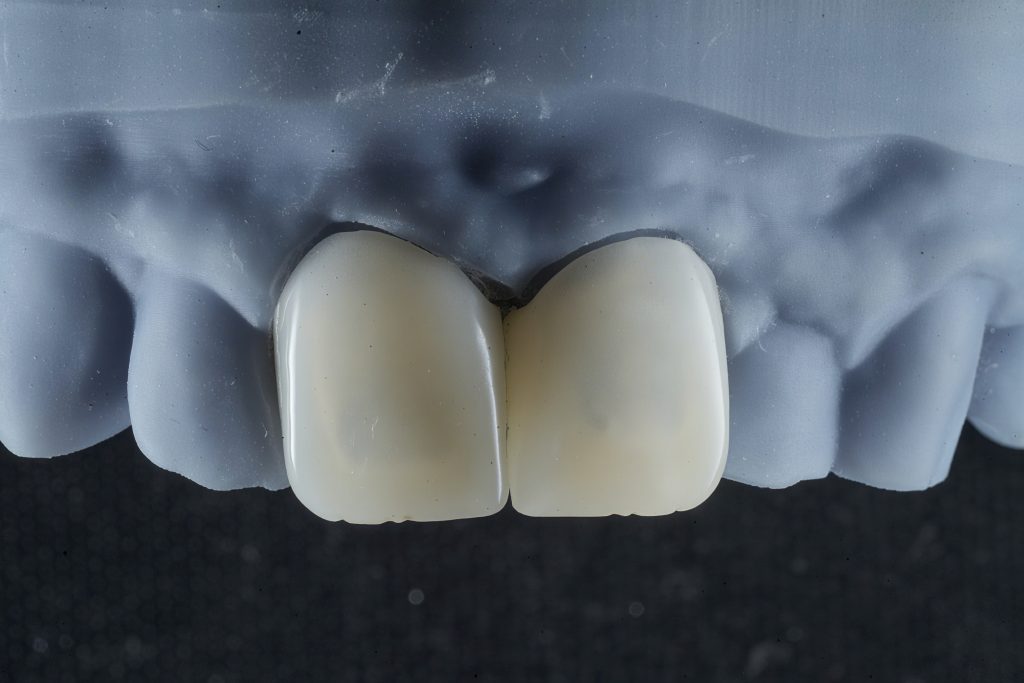

Step 3 — Conservative Emax Crown Preparation

All preparations were done under complete isolation.

- 1.0–1.2 mm labial reduction

- 1.5–2.0 mm incisal reduction

- Uniform chamfer finishing line

- Smooth internal contours

- Enamel preservation wherever possible

- Harmonized gingival zeniths

This ensured adequate thickness for lithium disilicate strength while preserving maximum tissue.

Step 4 — Shade Selection & Prototype Try-In

Using mock-ups and shade tabs:

- Cervical zones kept warm (A1–A2 region)

- Incisal translucency calibrated

- Midline, smile arc and phonetics evaluated with provisional crowns

- Adjustments incorporated into final Exocad design